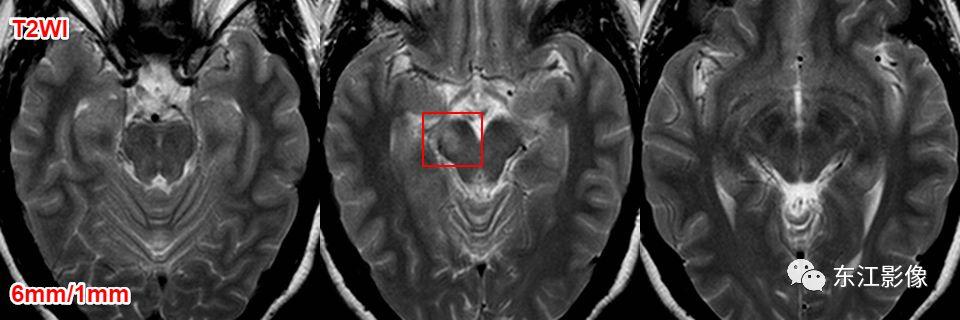

5. 脑脊液流动伪影

- 脑脊液流动伪影主要见于T2WI、FLAIR,主要是长TE序列容易出现流空效应的缘故。

- 但由于脑脊液流动方向、速率不一等因素的影响,呈现为非脑脊液信号影像,部分呈囊样。

- 常见于第三脑室、侧脑室室间孔旁区、脑干周围脑池(这些区域结构复杂)。

- 鉴别要点,T1WI、增强未能辨认;DWI与邻近一致的无信号;无占位效应。

侧脑室室间孔旁脑脊液流动伪影。

又一例。

桥前池脑脊液流动伪影。